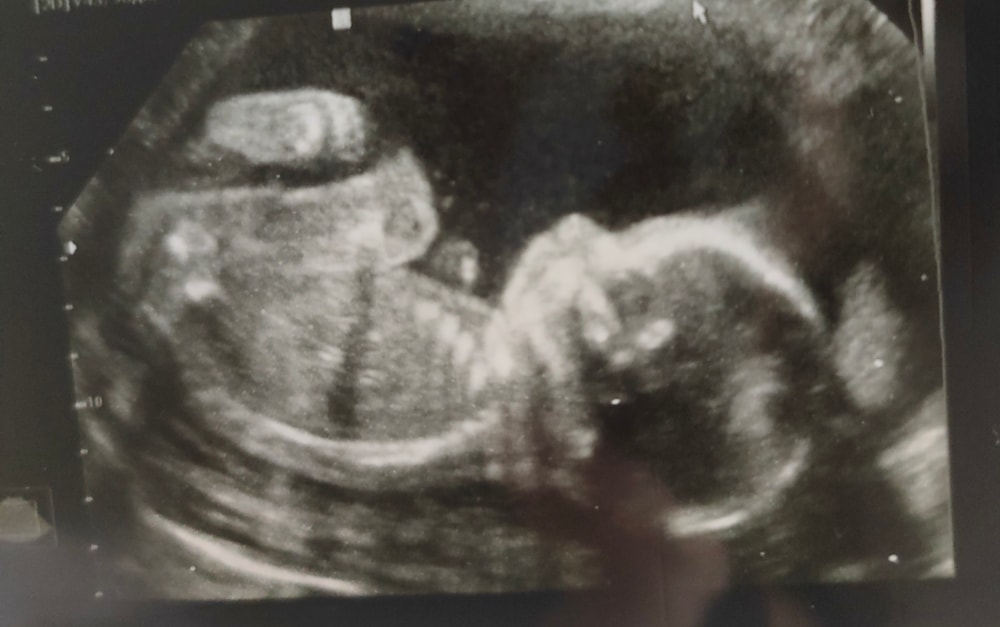

2 скрининг и экватор♥️

Ну вот наконец то и мы добрались до экватора, сегодня ровно 20 недель.

🌸13 августа успешно прошли 2 скрининг, никаких проблем не обнаружено🤞, срок по ПДМ 19.5, срок по КТР 20.3, ЧСС 152 уд/мин, вес 336 грамм. Шейка матки в порядке - 41 мм. Так же был пересмотрен риск преэклампсии, теперь 1:1030 (на 1 скрининге поставили 1:68), но кардиомагнил 150 мг и 1 гр кальцимина все равно продолжать пить для профилактики.

🌸И самое главное - у нас будет ДЕВОЧКА😍😍😍именно так, как мы с мужем и хотели (все таки не зря было отвращение к мясу во время токсикоза). Можно начинать покупать вещички и думать над именем.